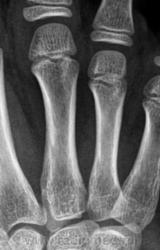

Остеоэпифизеолиз о/ф III пальца.

Спасибо Валентин Львович за обработку изображений, в данном случае остеоэпифизиолиз проксимальной фаланги 3п.. В косой проекции кстати даже четко видно ступеньку.